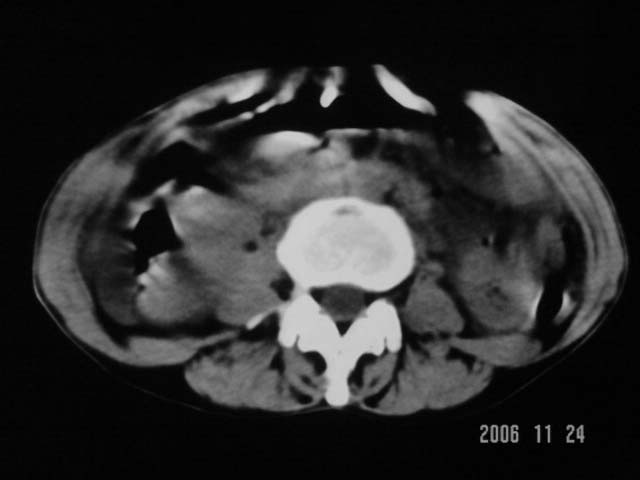

仰卧位见:肝前间隙及肝脾间隙内可见新月形气体密度影,边缘清楚,侧卧位见气体随体位改变而移动,ct值约-929hu。膈下、肝下间隙及部分肠间隙可见液性密度影。考虑:1、上腹部空腔脏器穿孔,以胃穿孔可能性大。2、少量腹水。

仰卧位见:肝前间隙及肝脾间隙内可见新月形气体密度影,边缘清楚,侧卧位见气体随体位改变而移动,ct值约-929hu。膈下、肝下间隙及部分肠间隙可见液性密度影。考虑:1、上腹部空腔脏器穿孔,结合临床,首先考虑胃穿孔可能性大。2、少量腹水

补充--肝门及肝肾间隙以见积气显示。

支持消化道空腔脏器穿孔(腹腔内大量游离气体影,小网膜囊内亦见气体影),少量腹水。